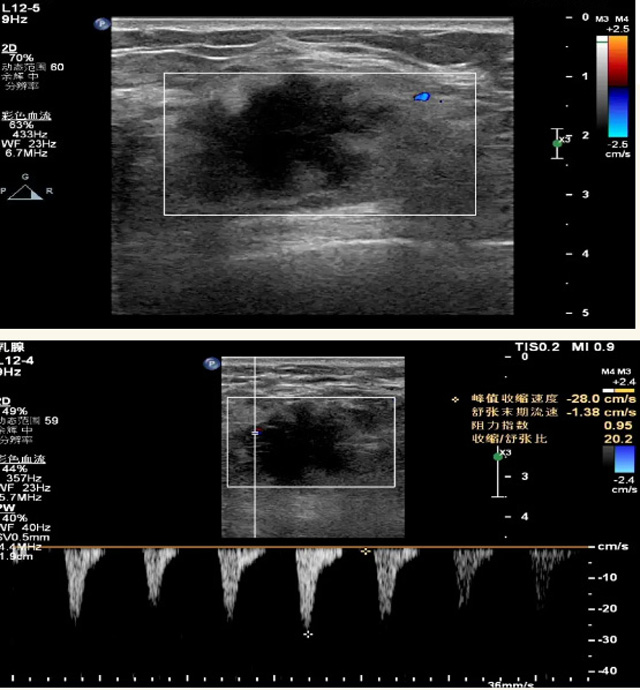

乳腺B超檢查無輻射,對(duì)囊性病變敏感,可以實(shí)時(shí)觀察病灶。超聲引導(dǎo)活檢跟手術(shù)前的定位。就是它對(duì)于微小的鈣化查出率比鉬靶稍微差點(diǎn)。磁共振MRI檢查也是是沒有輻射的,對(duì)備孕跟已經(jīng)懷孕的人士比較友好。不用擔(dān)心這個(gè)輻射影響胎兒?jiǎn)栴}。對(duì)乳腺病灶敏感性較高,致密乳腺病灶、乳腺癌的復(fù)發(fā),準(zhǔn)確鑒別囊性及實(shí)性病變??梢詭椭R床醫(yī)生判斷惡性、良性病變。但是MRI磁共振對(duì)微小鈣化不明顯,微鈣化還是鉬靶靠譜點(diǎn)。檢查時(shí)間比較長,有偽影的影響。費(fèi)用相對(duì)B超,鉬靶高很多。

乳腺B超